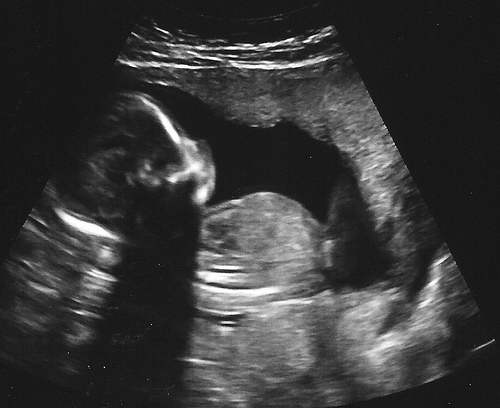

The fetal heartbeat can be detected through an ultrasound. You feel tired and may want to sleep a lot during the daytime.

The embryo is growing at a rate of about 1mm per day and the organs have formed. It’s recommended to get your first ultrasound.

The fetus is about 6cm long. Its fingers and toes have completely separated. From this week on, you should get regular prenatal examinations, including blood tests and ultrasounds.

The fetus starts to practice urinating. This week, your prenatal care should include routine examinations and an ultrasound.

By the end of this week, the fetus can be considered a full-term baby. Prenatal care for this week includes routine examinations and an ultrasound.